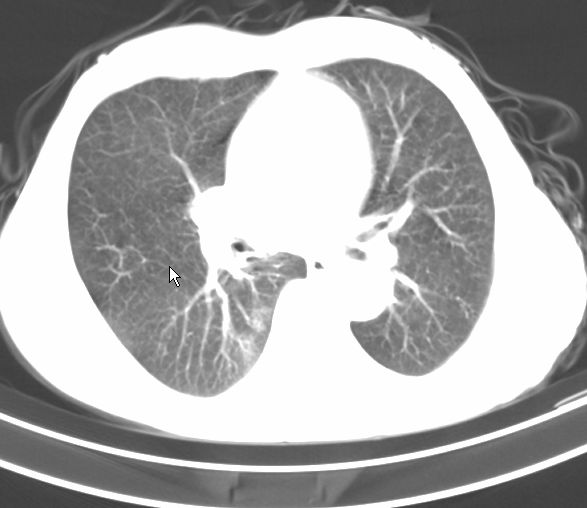

请大家看看是什么性质的。炎性病变首先考虑哪一种炎症。

支持右肺上叶前段\\下叶内基底段感染,建议抗炎治疗后复查,除外结核.

支持右肺上叶前段\\下叶上段感染,建议抗炎治疗后复查,除外结核.

支持右肺上叶前段、下叶内基底段感染,建议抗炎治疗后复查,除外结核.

右肺上叶前段及下叶内基底段感染性病变;建议抗炎治疗后复查。

楼主说是炎症,凭啥?典型的周围型肺癌(腺癌可能性大),肝内可能已有转移,强化看看吧。